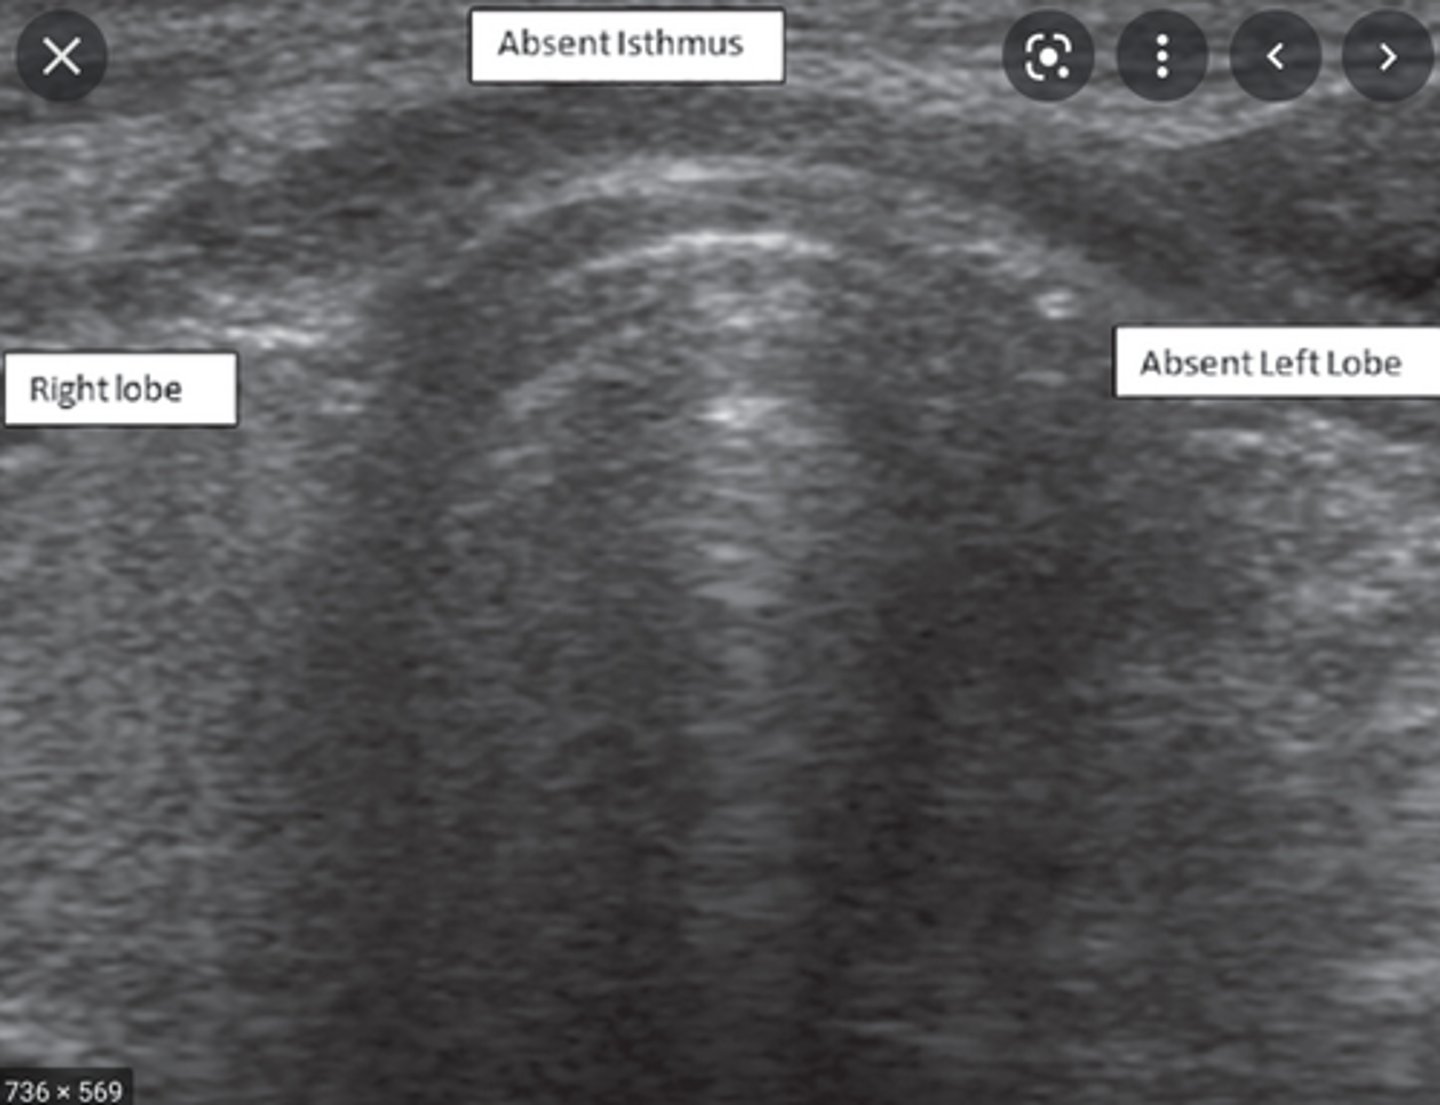

The following describes which congenital anomaly of the thyroid?:

-Thyroid consists of two distinct lobes

Absent Isthmus

Anatomy of the Thyroid Glands:

-Largest _____ gland in the human body

-Divided into the right and left lobes with a connecting _____

-_____ lobe is usually larger than the _____

-Divided into the right and left lobes with a connecting isthmus

-Right lobe is usually larger than the left

-Isthmus connects the lower third of the thyroid lobes